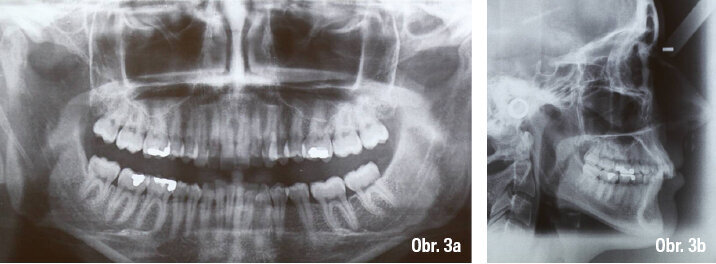

Na telerentgenu pacientky byla diagnostikována II. skeletální třída, protruze horních řezáků a inklinace dolních lingválně. Na ortopantomogramu byla zjevná ztráta 36, úroveň kosti a celkový biologický faktor chrupu byly vyhovující (obr. 3a–b).